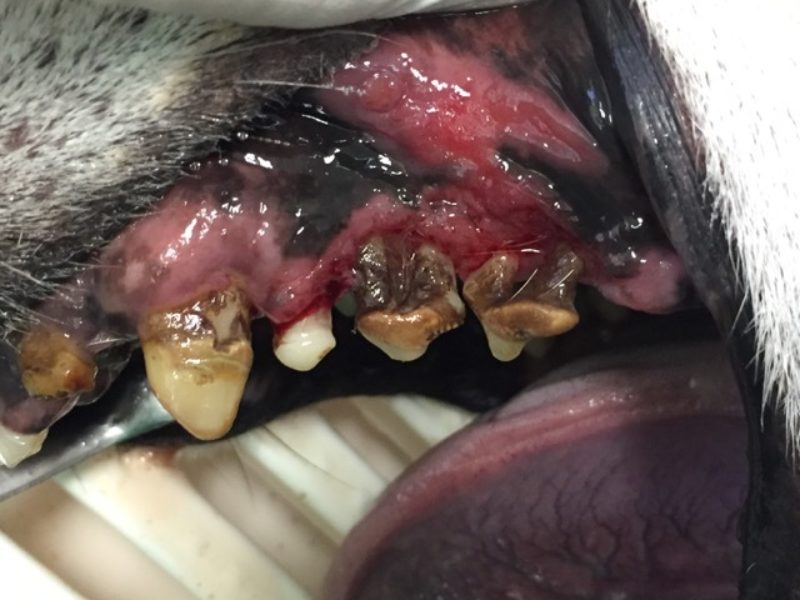

Durch den Zahnstein kommt es schließlich zu Entzündungen des angrenzenden Zahnhalteapparates. Zahnfleisch- und Knochenschwund erleichtern dem Zahnstein, sich noch weiter auszubreiten. Die zum Teil frei liegenden Zahnurzeln werden nun ebenfalls befallen. Dort wird der Belag allerdings als Konkrement bezeichnet und führt dazu, dass der Zahn keinen Halt mehr hat.